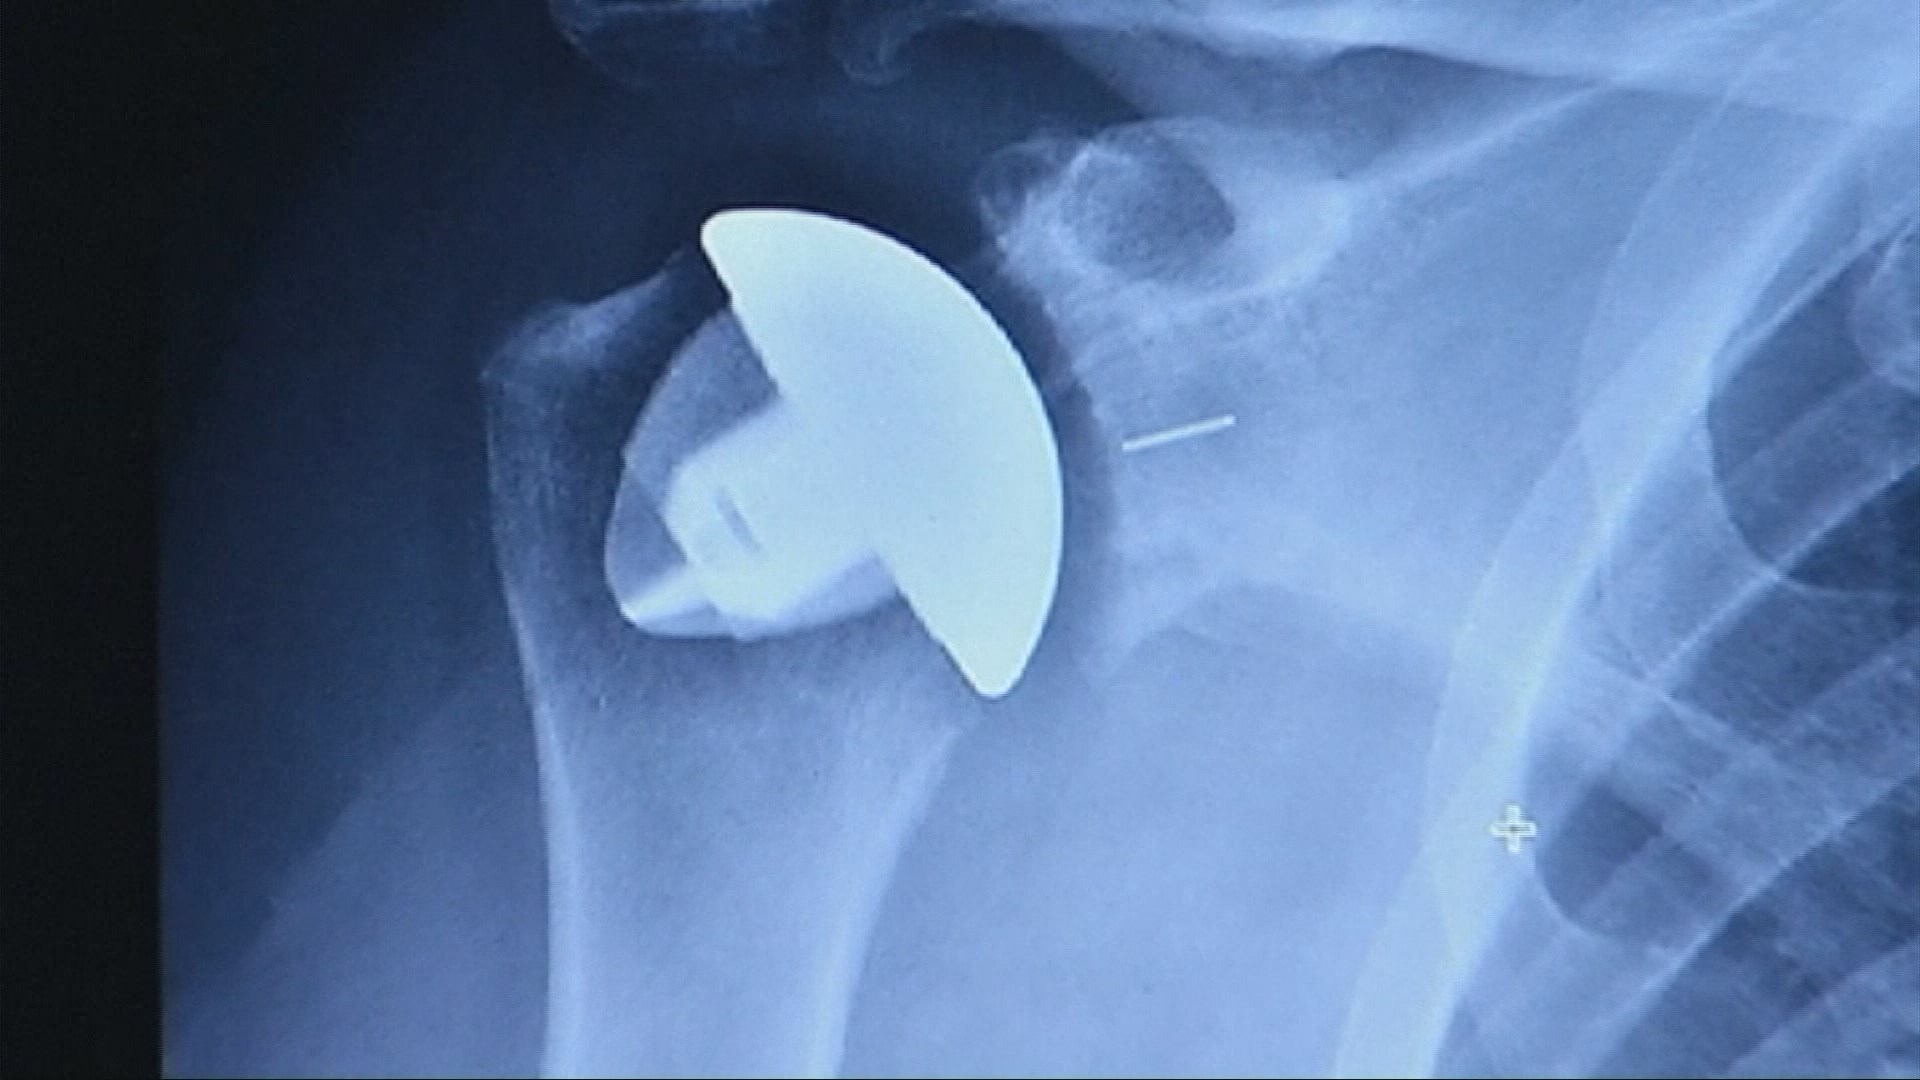

Osteoarthritis Joint Shoulder Replacement . A shoulder replacement is a procedure that tries to eliminate the source of pain and dysfunction by replacing damaged parts of the shoulder joint with artificial components called. The main types include arthroscopy and total shoulder replacement. Several conditions can cause shoulder pain and disability, and lead patients to consider shoulder joint replacement surgery. But more than 50,000 shoulder replacements are done in the. Shoulder replacement surgery is less common than hip or knee replacements. It usually occurs in people 50 years of age and older, but it may occur in younger people, too. Also known as a partial shoulder replacement, this surgery involves either replacing your damaged humerus or arm bone portion while the glenoid portion of your shoulder joint is intact or. Through surgery, the shoulder joint may be entirely replaced, part of the joint might be resurfaced, or excess bone may be removed to reduce pain and. Surgeons may perform osteoarthritis shoulder surgery in severe cases of osteoarthritis. Total shoulder replacement, also known as total shoulder arthroplasty, is a procedure where portions of the bones in the shoulder joint are removed and replaced with artificial implants.

Surgeons may perform osteoarthritis shoulder surgery in severe cases of osteoarthritis. Total shoulder replacement, also known as total shoulder arthroplasty, is a procedure where portions of the bones in the shoulder joint are removed and replaced with artificial implants. Several conditions can cause shoulder pain and disability, and lead patients to consider shoulder joint replacement surgery. But more than 50,000 shoulder replacements are done in the. Shoulder replacement surgery is less common than hip or knee replacements. The main types include arthroscopy and total shoulder replacement. A shoulder replacement is a procedure that tries to eliminate the source of pain and dysfunction by replacing damaged parts of the shoulder joint with artificial components called. Through surgery, the shoulder joint may be entirely replaced, part of the joint might be resurfaced, or excess bone may be removed to reduce pain and. It usually occurs in people 50 years of age and older, but it may occur in younger people, too. Also known as a partial shoulder replacement, this surgery involves either replacing your damaged humerus or arm bone portion while the glenoid portion of your shoulder joint is intact or.